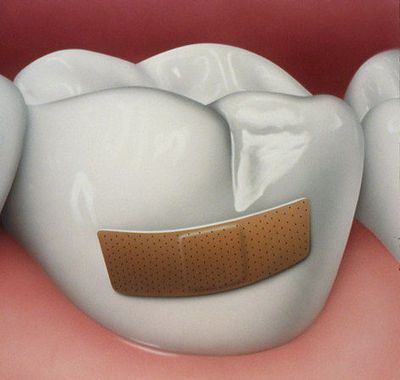

Fagylalt fagylaltkehely a szó pecsét

Eltávolítása után szuvas szöveti készített üreg gyógyszeresen kezelt antiszeptikus készítmények és lezárjuk. A kezelés sikere nagyban függ a megfelelő kiválasztása a töltőanyag. Ő nemcsak biztosítja a hosszú élettartamot, a helyreállítás, hanem, hogy biztonságos legyen az emberi egészség és megfelel a beteg esztétikai elvárásoknak.

Egy másik, hogy a tömítés lehet egy lapon, ami gyártja a fogtechnikai laboratóriumban, és tartják megbízhatóbb és esztétikus megoldás. A kezelés bonyolult szuvasodás, ha a fogat elpusztult több mint 70%, célszerű, hogy egy koronát.